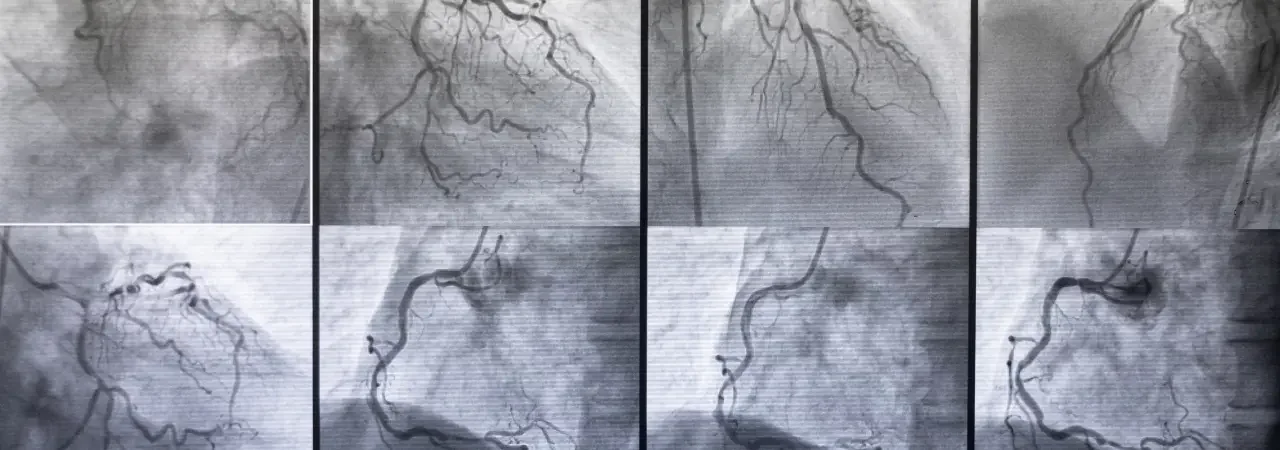

- Önce kontrastlı BT anjiyografi ile merkez hattı boyunca ölçüm yaparız. Bu ölçümler boyun uzunluğu, çaplar, açılar ve iniş-zemin yeterliliğini içerir.

- Perkütan femoral giriş yaparız. Kılavuz tel ile ana gövde ve uzatma parçalarını yerleştiririz. Floroskopi ve anjiyografi ile pencereleri koruruz. Bu pencereler renal, visseral ve arkus dallarıdır.

- Son anjiyografiyle sızdırmazlık, graft appozisyonu ve distal perfüzyon doğrulanır; gerekli ise balonla post-dilatasyon uygulanır.